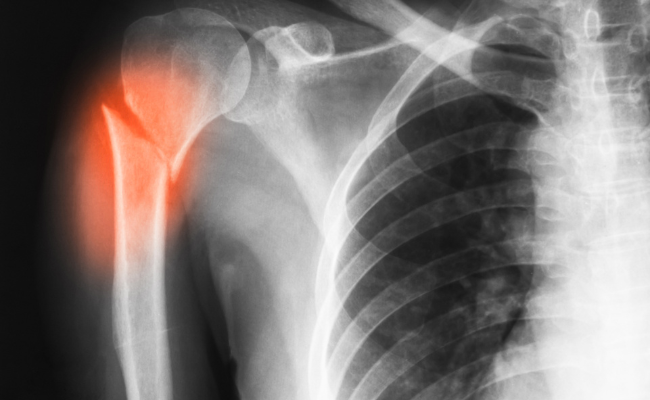

A comminuted fracture is a severe type of bone fracture that occurs when a bone breaks into multiple fragments or pieces. This is in contrast to a simple fracture, where the bone breaks into two pieces or a few large fragments. Comminuted fractures are often the result of high-energy trauma, such as car accidents, falls from heights, or sports injuries. These fractures can occur in any bone in the body, but they are more common in long bones, such as the femur, tibia, and humerus.

2. X-rays: X-ray images are commonly used to visualize the fractured bone and assess the degree of fragmentation.